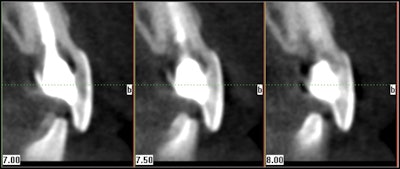

With the different cone-beam CT machines and fields-of -view available, dentists can determine which machine is most appropriate for their practice. A cone beam system with a small field-of-view is especially helpful when viewing one to three teeth maximum. The quality of the images with this machine is beneficial in diagnosing single problematic areas, particularly in resorption defects, fractures, and retreatment cases.

An advantage to large fields of view would be to determine symmetry. Occasionally there will be a lesion present and the need for a scan on the opposite arch is helpful in determining if it is normal. Also when there are difficult teeth to treat, a full scan of one arch can be helpful in determining whether extra canals are truly evident. For example, a retreatment case that is difficult to determine if a 2nd, 3rd, or 4th canal is present due to the prior treatment can also be viewed with its counterpart. If a canal is demonstrated in its counterpart, there will surely be one in the case in question.

| Cone beam CT images can provide axial views not possible with traditional 2D imaging. |